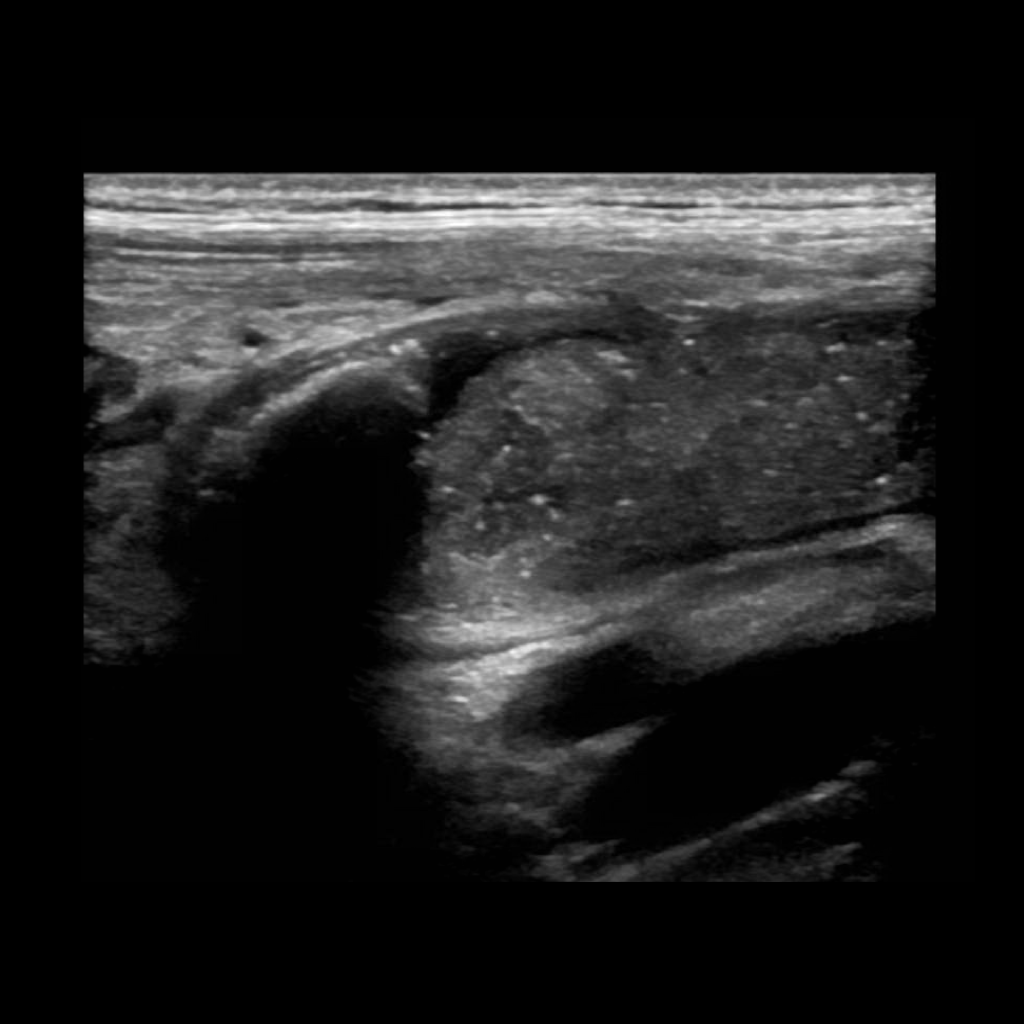

Appendicitis 3

0.9 cm appendicitis curled on itself with, fat stranding trace free fluid.